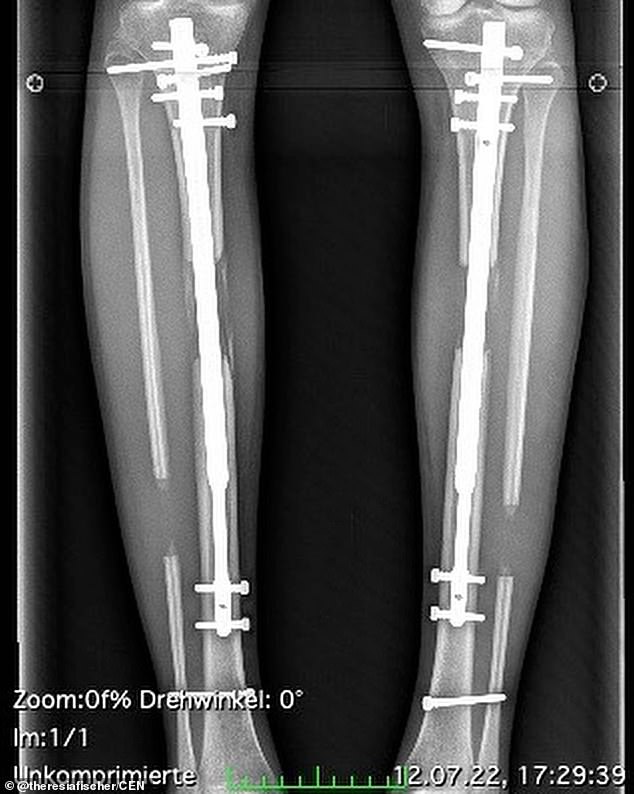

Today, her legs have telescopic rods in the shinbone area. It was long, extensive, painful, and just not worth it, she adds. Did we mention the amount of physiotherapy and recovery time required to get back on her feet again?